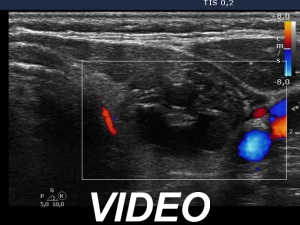

Ultrasonography. The thyroid was echonormal. There was a moderately hypoechoic nodule in the right lobe. The lesion presented halo and both perinodular and intranodular blood flow. The dimensions were 18x11x20 mm, width, depth, length, respectively. The left lobe had a cystic nodule which presented back wall cystic figures but not microcalcifications. The dimensions were 18x16x27 mm, width, depth, length, respectively.